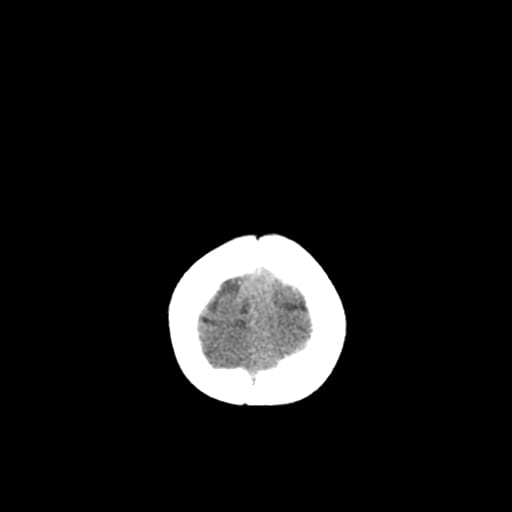

Age: 1

Sex: Male

Indication: Fall